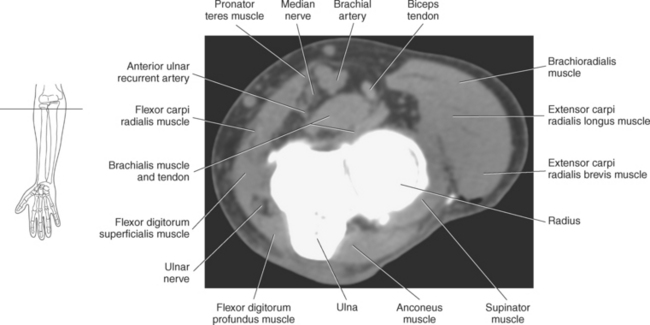

One method to classify the muscles of the forearm is to use the radius, ulna, and interosseous membrane to divide them into a ventral group (the flexors) and a dorsal group (the extensors). The two groups can be further divided into superficial and deep muscles. The muscles of the forearm are described in Table 9.5.

All five of the superficial muscles in the ventral group have an origin from the common flexor tendon off the medial epicondyle of the humerus. These muscles are demonstrated in Figures 9.86 through 9.98.

The muscles of the superficial dorsal group are demonstrated in Figures 9.87 through 9.98 and 9.100. The brachioradialis is an extensor muscle lying along the lateral border of the forearm. This large muscle arises from the upper two thirds of the supracondylar ridge of the humerus and attaches distally to the radial styloid process. The brachioradialis flexes the forearm at the elbow and assists with pronation and supination (Figure 9.100).